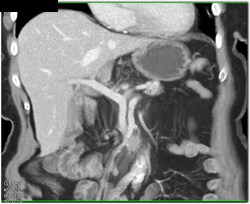

Diagnosis

Top Normal Gland